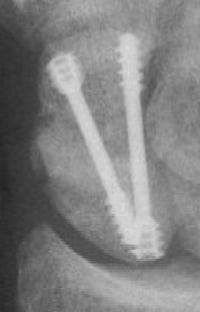

Case 7. This nonunion patient's scaphoid and iliac crest were unusually soft bone.

Click for larger image

After two screws, the fixation was clearly inadequate, so I put a third screw through the graft into the proximal pole. I wasn't sure whether to buy

stock in Herbert screws or Zantac. The fracture healed despite AWOL and no immobilization.